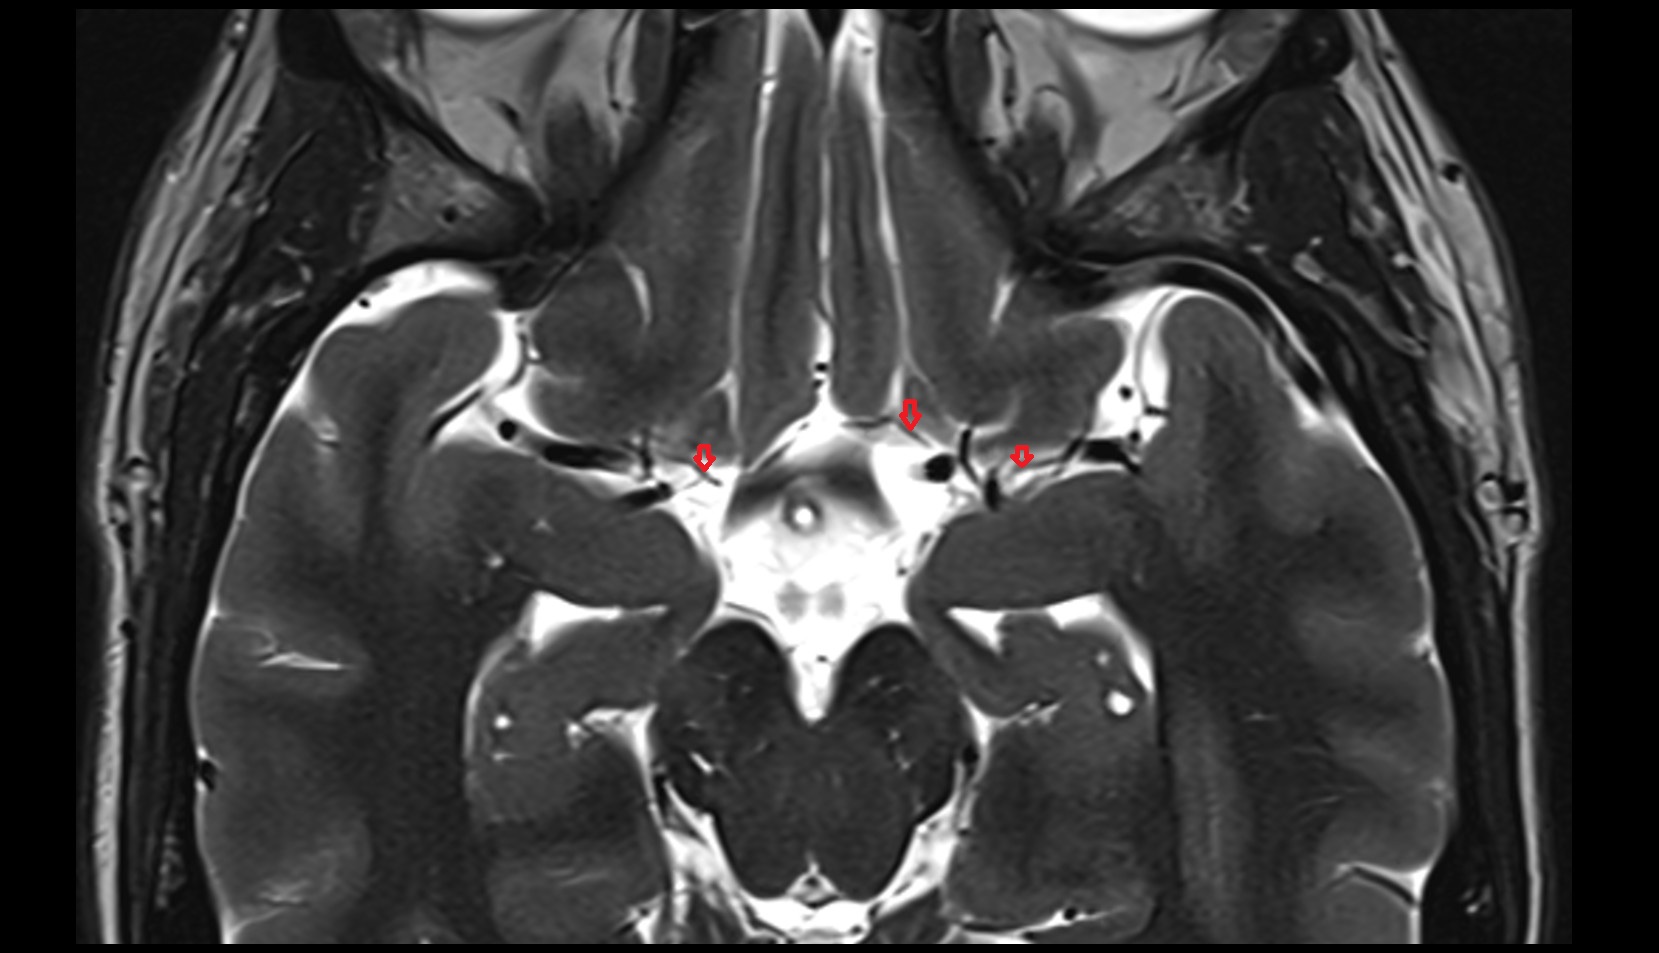

- Hippocampus

- Body of hippocampus

- Head of hippocampus

- Tail of hippocampus